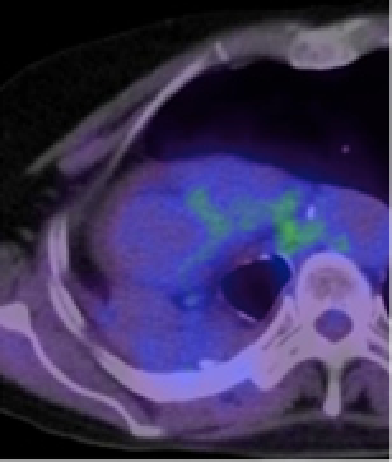

治療前

治療中

治療後

肺がんの胸壁再発の患者さんで、治療後にPETの赤い色が消失しています。痛みもなくなりました。